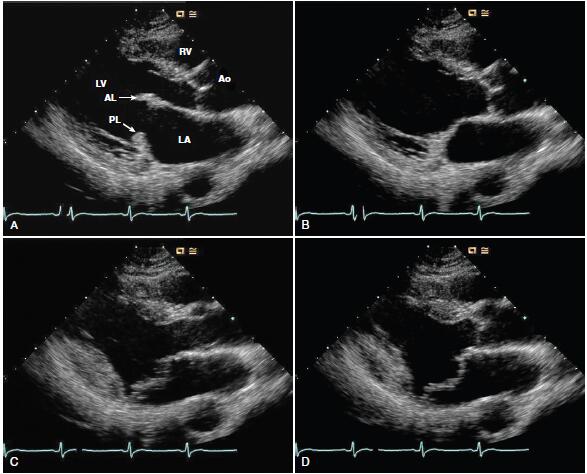

所谓的二尖瓣脱垂,指的是在心脏收缩期,二尖瓣脱入左心房(图1),多数的二尖瓣脱垂患者,于体检时发现收缩中晚期的敲击音,而后经心脏超声确诊。如在左室长轴切面,二尖瓣脱入左心房超过二尖瓣环平面2 mm,即可确诊MVP的诊断(图2)。

图2 心脏超声可见左室收缩时二尖瓣脱入左心房,超过二尖瓣环平面2mm以上